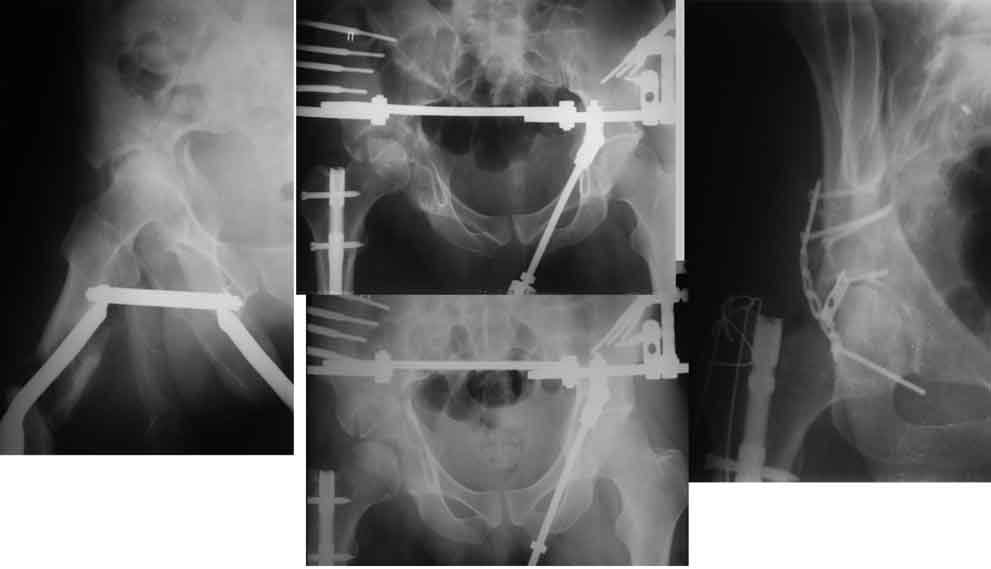

Пример с антеградным введением стержня (застарелый случай)

У тебя тоже можно воспользоваться этой методой, однако настоятельно рекомендую ЗИМО делать в аппарате (дистракционном устройстве) и лишь потом открыто вертлугу.

Глубокоуважаемые коллеги! Благодарю за полезные советы, которые нам очень помогли в выборе оперативной тактики пациента. 13.02.08 мы выполнили первый этап оперативного лечения этого больного. Вначале зафиксировали левое бедро АВФ Гофмана

(главный травматолог области достал из каких-то «анналов», первый раз в жизни увидел этот аппарат в живую). После наложения «ДРУ Челнокова» выполнили ЗИО правого бедра реконструктивным штифтом Chm. Далее уложили пациента на левый бок и выполнили остеосинтез вертлужной впадины. Ограничились задне-латеральным доступом без отсечения вертела, чтобы не утяжелять операцию. Результат прилагается.

Следующим этапом планируем выполнить ЗИО левого бедра.